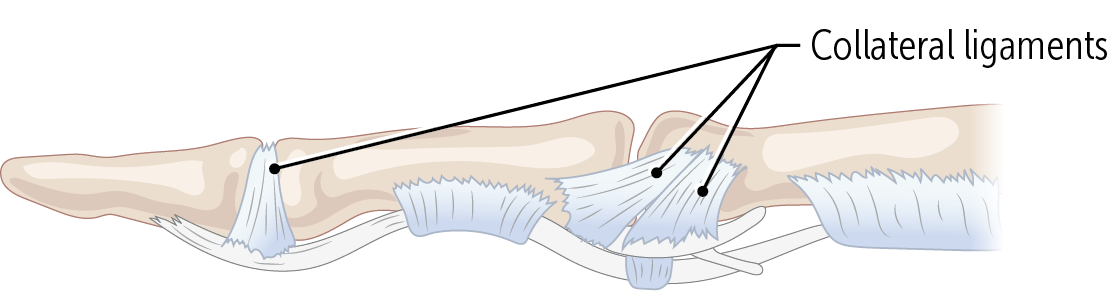

The PIP and DIP joints are very stable laterally, since the joints have strong _____________ supporting them.

collateral ligaments

Finger sprains are often caused by jamming the finger against something, hyperextending the _________ joint.

PIP or DIP (proximal and distal interphalangeal joints)